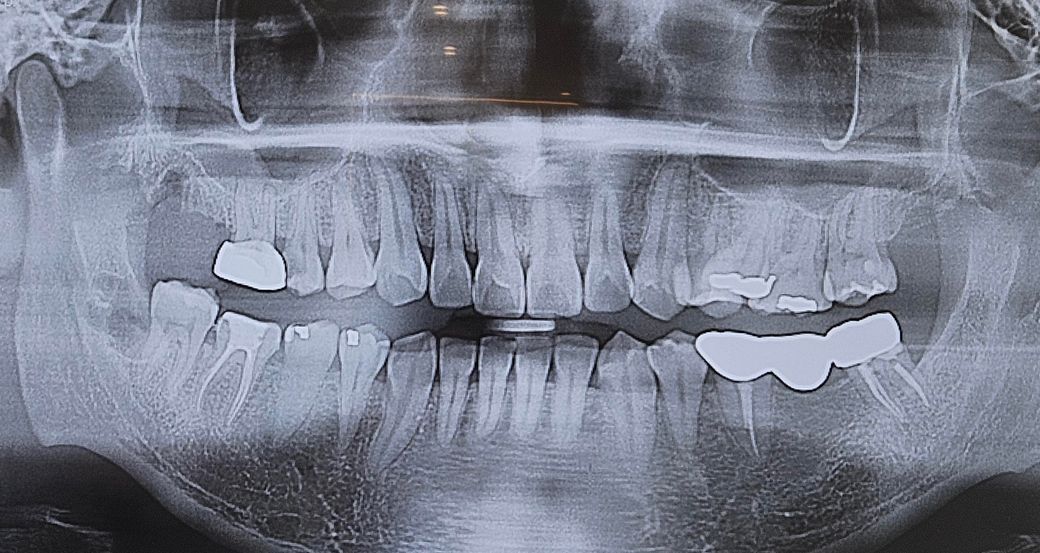

왼쪽 위 제2소구치(엑스레이 상 오른쪽 위)는 현재 맹출에 있어서 공간이 부족해서 옆 어금니랑 겹쳐 나왔고 이런 경우 원활한 구강위생관리를 위해 그리고 인접 치아의 치근(뿌리)흡수를 방지하기 위해 발치하고 교정으로 재배열을 해주는 치료가 필요할 수 있습니다.